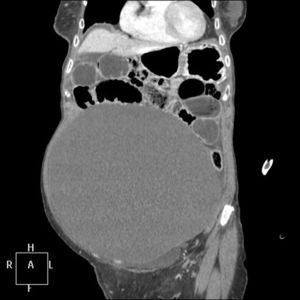

The patient is a 92-year-old woman, with no medical-surgical history of interest, who reported abdominal pain and fecal vomiting over the previous 24h. Upon examination, the abdomen was diffusely painful, with no peritoneal irritation, epigastric tympanites and dullness to percussion in the rest of the abdomen. Computed tomography detected an abdominal cystic mass measuring 22×14cm that occupied the entire abdomen and caused obstructive symptoms of the small intestine (Fig. 1). The patient was treated with emergency surgery, which revealed obstruction of the small intestine secondary to a mass dependent on the mesosigmoid (Fig. 2). Sigmoidectomy was carried out with exegesis of the lesion, with primary colorectal anastomosis. The pathology diagnosis was mesenteric cyst, 22×16cm and 4.2kg.